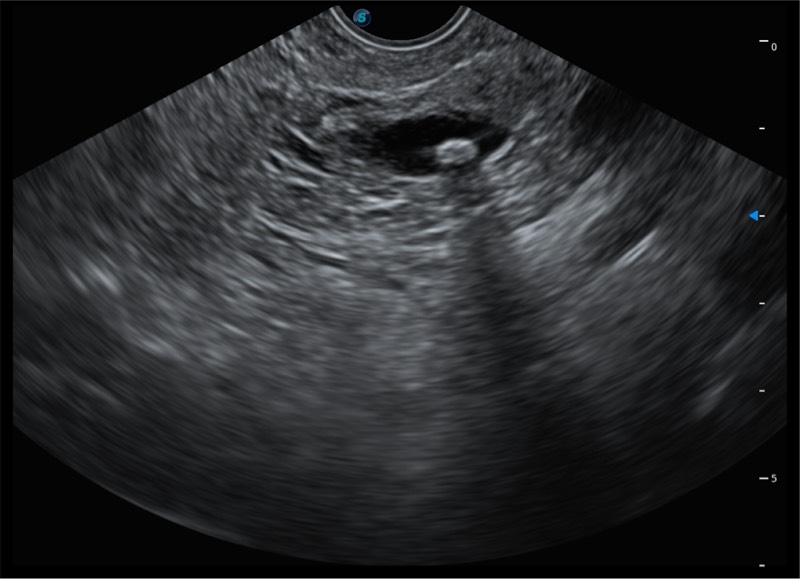

搭载百万级CMOS成像技术

及自主研发凸阵换能器,

可呈现优质的内镜和超声画面

基于二十年的超声技术积累,球速体育入口提供了最新一代的独立超声主机,在提供高质量图像的同时满足多学科使用。具备常见多普勒技术并提供弹性成像、声学造影等高端影像技术。新一代传感器具有更强的抗干扰能力并减少图像伪影。

150°超声扫描角度

4-12MHZ宽频输出